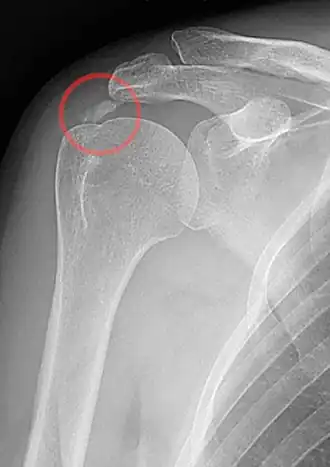

Tendinite calcifiante de la coiffe des rotateurs

Les dépôts de calcium sont visibles en radiographie formant une tache opaque au niveau de la localisation du tendon concerné. L'échographie peut également être utile et est fortement corrélée avec le stade de la maladie[1].